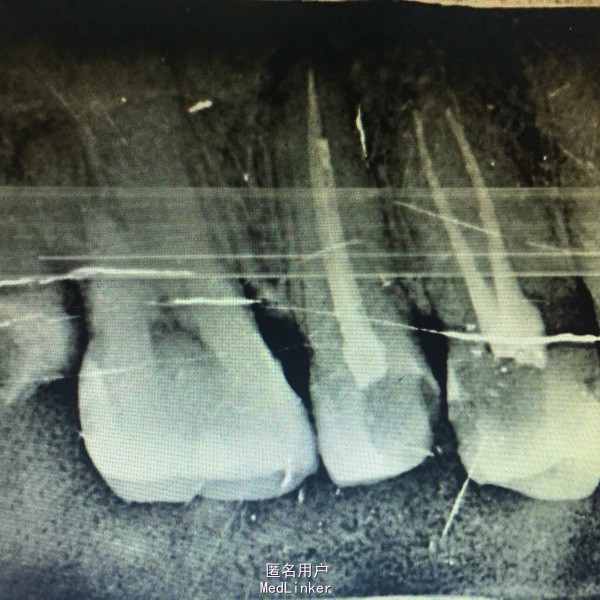

查体:14,15邻面之间龋坏,洞底有大量软化牙本质,探(+),冷热诊疼痛明显且持续较长时间。叩(-),X线示龋坏深达牙髓腔。17,37残冠,26牙合面大面积龋坏,探(+)冷(+)叩(-),X线示龋坏深达髓腔。 患者血压,血糖在正常范围,其余满足拔牙适应症。

诊断:14,15,26牙髓炎17,37残根 治疗: 局麻下14,15去腐,开髓揭髓顶降牙合,冲洗髓腔,拔髓疏通根管,测量根管配合EDTA进行根管预备,次氯酸钠进行根管冲洗,吸潮纸尖拭干根管,进行根管试尖,X线示恰充,进行热牙胶垂直加压连续波充填法进行根管充填。暂封观察进行树脂嵌体修复。分次拔除17,37.嘱拔牙后注意事项。